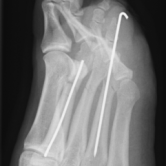

Röntgenbilder